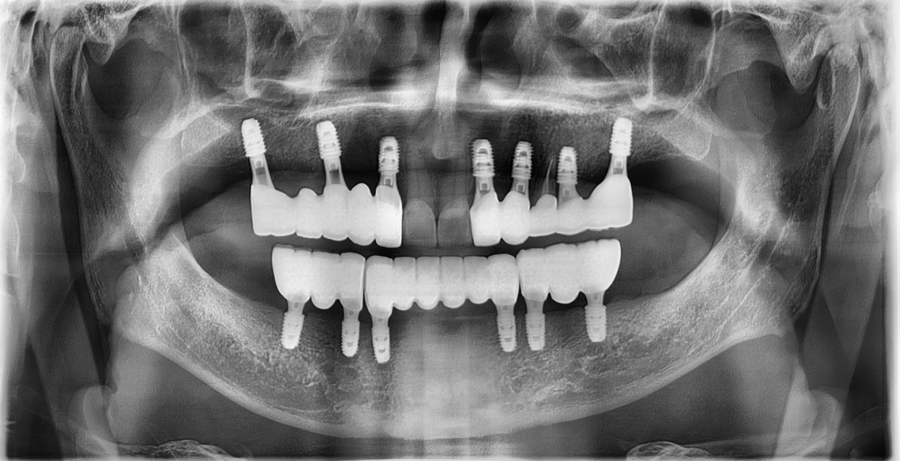

Detailed diagnosis

At our Jamsil dental clinic, Seoul OB Dental Hospital,

even senior patients are carefully assessed for their current dental condition

through a 3D scanner, intraoral endoscopy, and bite examination.

The examination showed that

enough tooth structure remained in the front teeth,

so veneers could be done without excessive reduction,

and the gum condition was also stable.

The bite was also well aligned without any major issues,

so this was a case in which improving only the color and shape of the existing prosthetics

could restore a more natural and balanced front tooth line.